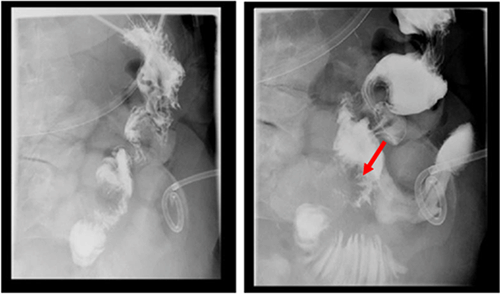

Interventional radiology (IR) was consulted for drainage catheter placement. After placement, the catheter drained biliary contents raising the suspicion of different underlying pathology. The drain was interrogated, revealing a small fistulous tract between the abdominal collection and small bowel near the duodenojejunal anastomosis (Figure 1).

Figure 1. IR Drainage Catheter Placement. Published With Permission

UGIS confirmed the fistulous collection (red arrow) between the efferent limb of the duodenojejunostomy and the abscess (Figure 2). Of note, four months prior, the patient was diagnosed with recurrent adenocarcinoma that had metastasized to intra-abdominal lymph nodes, both lobes of the liver, right lower lobe of the lung, right lung hilum, and left lower neck lymph nodes. The patient was then started on salvage chemotherapy with gemcitabine/Abraxane®. After extensive discussions with the patient and her family, the decision was made to attempt endoscopic management of the fistulous tract.

Figure 2. Upper GI Series Confirming Fistulous Collection Between Efferent Limb of Duodenojejunostomy and Abscess. Published With Permission